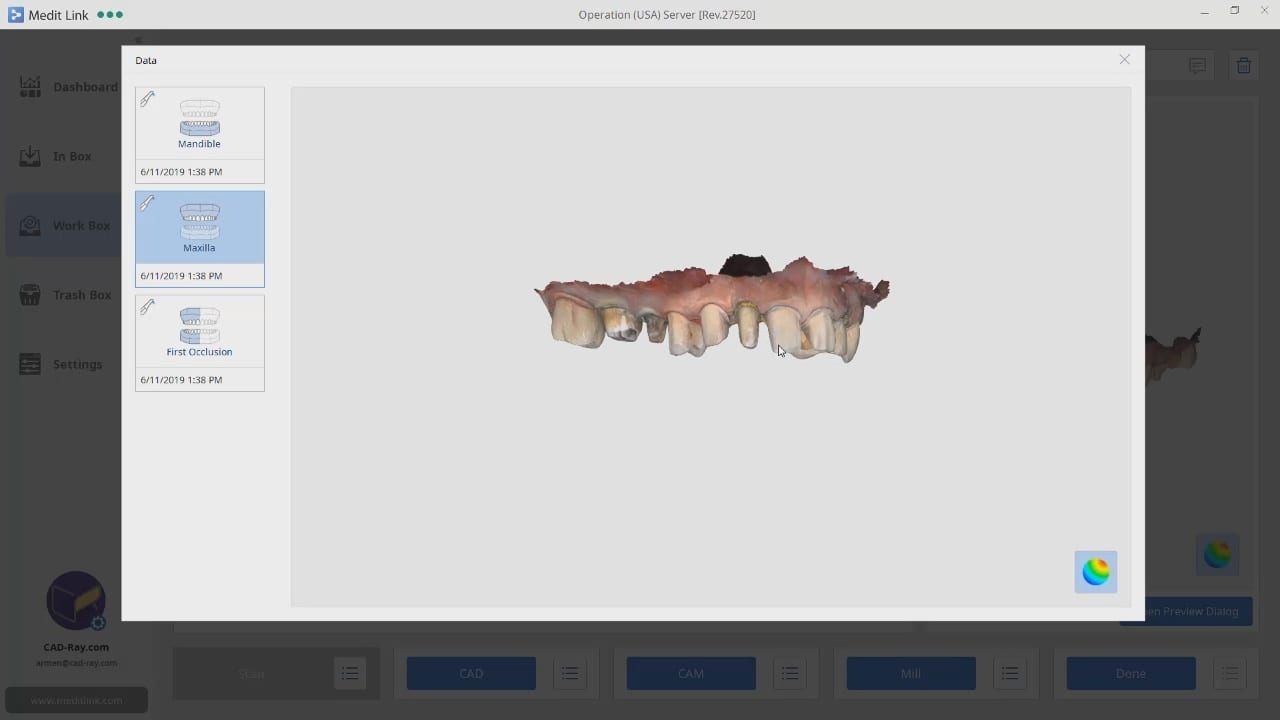

upper and lower models related to each other for design